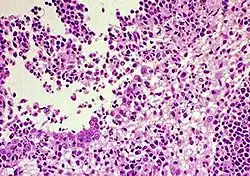

FIP-infected kidney showing inflammatory response | |